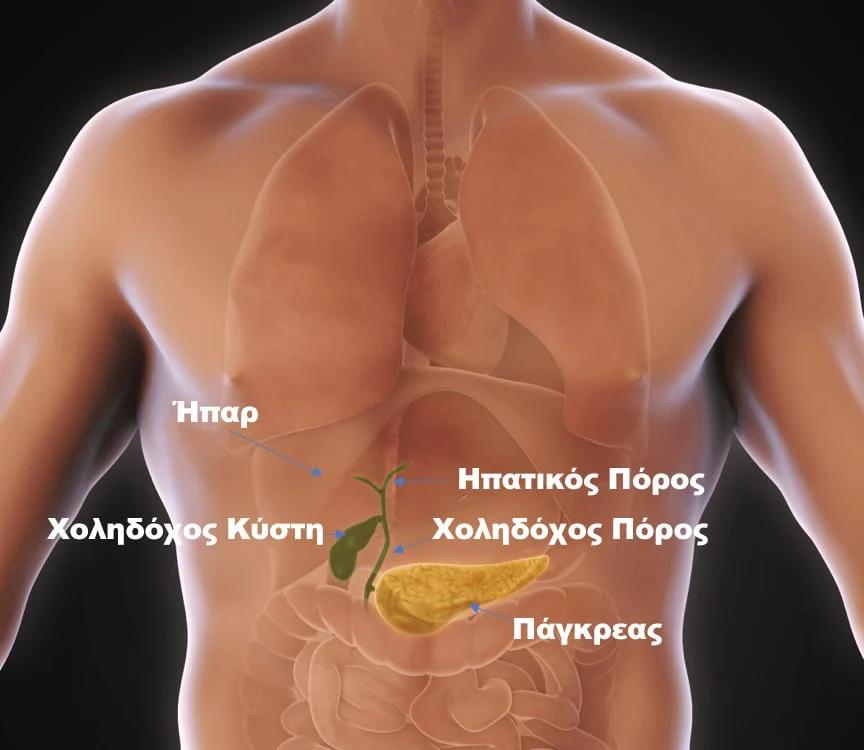

Η χοληδόχος κύστη, ένα μικρό όργανο που βρίσκεται κάτω από το ήπαρ, συνδέεται στενά με αυτό μέσω του χοληδόχου πόρου.

Η κύρια λειτουργία της είναι να αποθηκεύει τη χολή, ενεργώντας ως επιμελής φύλακας που εκτελεί σιωπηλά τον ζωτικό της ρόλο στο σώμα.

Όταν απολαμβάνουμε νόστιμο φαγητό, η χοληδόχος κύστη συστέλλεται, στέλνοντας τη χολή στο δωδεκαδάκτυλο για να βοηθήσει στη διάσπαση των λιπών. Η χολή έχει επίσης αντιβακτηριακές ιδιότητες, λειτουργώντας ως μια αόρατη αμυντική δύναμη της υγείας που διατηρεί την υγεία του πεπτικού συστήματος.

Κοινοί λίθοι του χοληδόχου πόρου

Μόλις αφαιρεθεί η χοληδόχος κύστη, ο κοινός χοληδόχος πόρος αναλαμβάνει το ρόλο του. Ωστόσο, χωρίς την χοληδόχο κύστη να αποθηκεύει τη χολή, η πίεση στον κοινό χοληδόχο πόρο αυξάνεται, προκαλώντας αντισταθμιστική διαστολή. Αυτή η παρατεταμένη στασιμότητα της χολής αυξάνει τον κίνδυνο εμφάνισης λίθων του χοληδόχου πόρου.